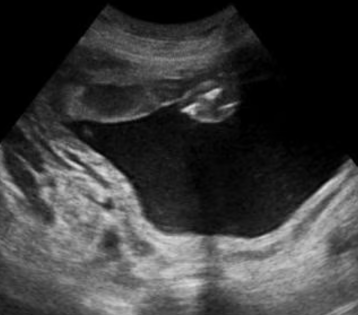

Cordocentesis (Fetal Blood Sampling)

It is also known as percutaneous umbilical blood sampling or fetal blood sampling,is a prenatal diagnostic procedure that involves extracting a small sample of blood from the fetal umbilical cord

Timing of procedure : 19 weeks onwards